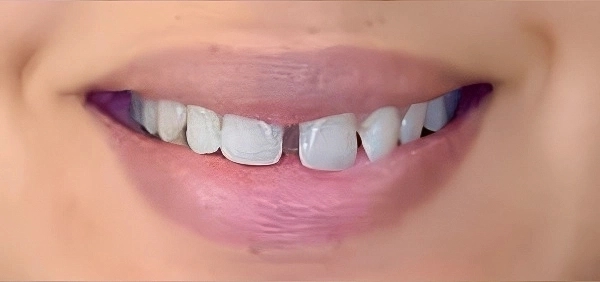

Spacing

Crowding

Protrusion

Bite Issues